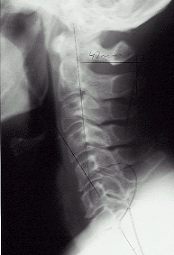

A brief physical exam will be performed in accordance with your chiropractor's clinical judgment. In addition, a careful spinal examination and analysis will be performed to detect any structural abnormalities that may be affecting or causing your condition. If necessary, the patient may be sent for x-rays as well. All of these elements are important components of your total health profile, and vital to the chiropractor in evaluating your problem.